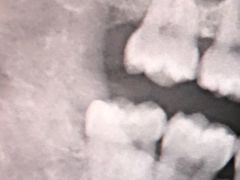

• 上海市第七人民医院

• -上海市第七人民医院